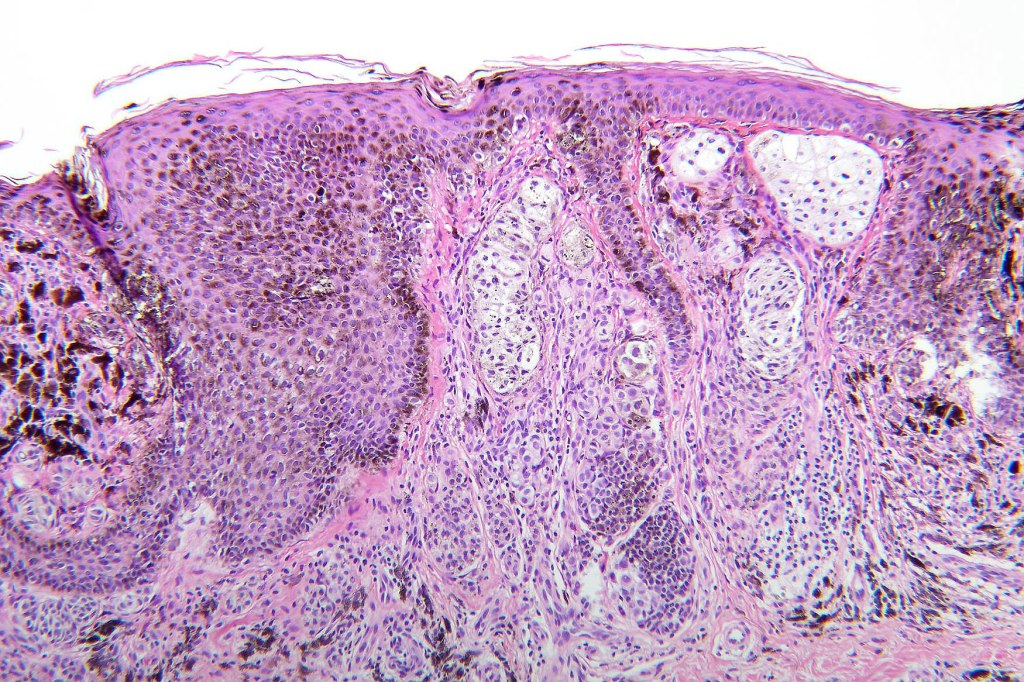

Histological features

•May affect the tumor in part or whole

•Enlarged cells with copious eosinophilic, foamy or clear cytoplasm (some authors include melanoma with clear cell change in the same category)

•Variable pigmentation

•Nuclei vesicular or hyperchromatic

•Pleomorphism is not generally marked and indeed can be very subtle

•Thought to be a result of abnormal or degenerative melanosome change